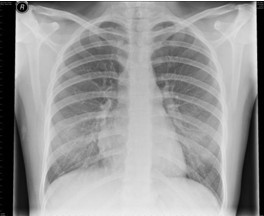

4.胸部X線檢查 哮喘發(fā)作時(shí)兩肺透亮度增加,呈過度充氣征象:并發(fā)肺部感染、肺不張、氣胸時(shí)出現(xiàn)相應(yīng)X線征象。

【題】下列哪項(xiàng)描述符合哮喘發(fā)作時(shí)典型的X線表現(xiàn)

A.兩肺透亮度增加,呈過度充氣征象

答案:本題選A。